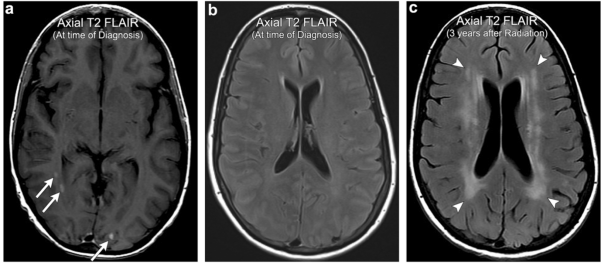

案例4:颅内转移瘤放疗后出现放射性脑白质脑病

47岁女性,有多发性颅内甲状腺癌转移的病史(箭头)。患者接受全脑放疗后,在随后的几年里,逐渐进展出现认知能力下降。全脑放疗3年后的影像显示广泛的脑室周围T2 FLAIR高信号(箭头所指),比预期的与年龄相关的微血管疾病广泛,符合放射性脑白质病。注意皮质下U纤维的相对保留。